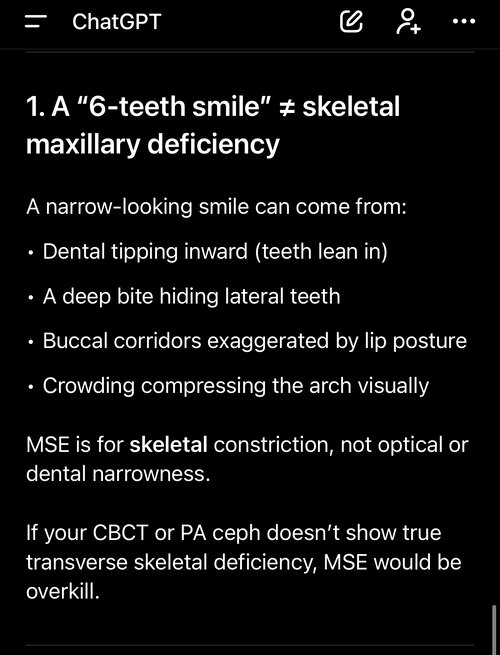

i have a bad deep bite with a fairly narrow plate i dont have any breathing issues or nothing tho im worrying about, because i dont want to get fucked over and have my maxilla pushed back any solutions? and if so will any of these solutions cause problems and or be a issue in the future?